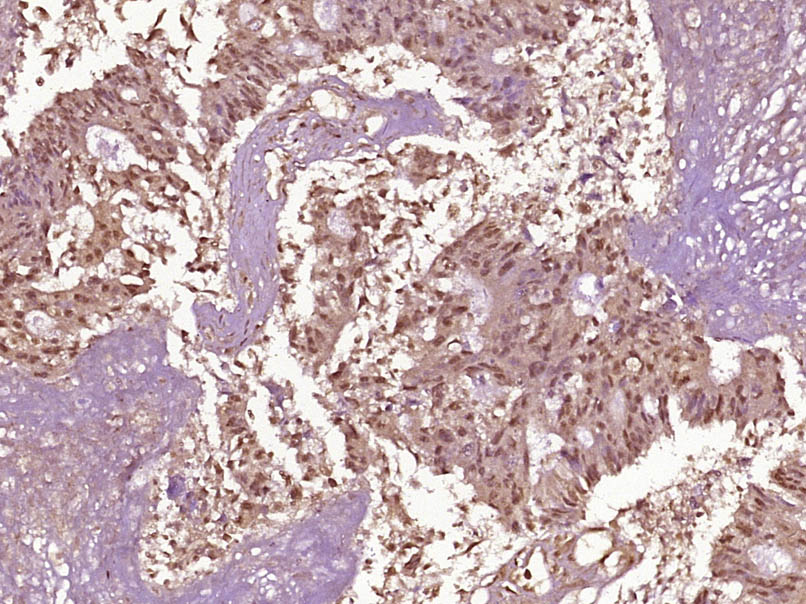

| IHC-P | Human, Rat | Mouse, Pig, Cow, Dog | 1:100-500 |